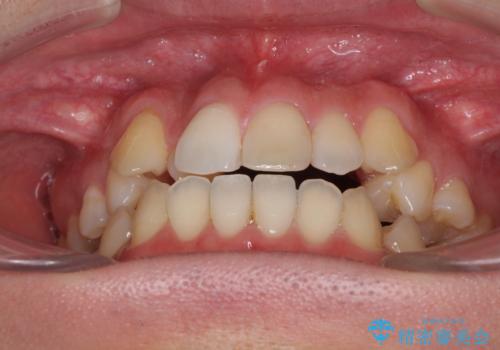

左右の八重歯が気になる ワイヤー装置での咬み合わせ改善

- 八重歯と前歯のデコボコを気にして来院された患者様です。

舌の突出癖がなかなか改善されず、上下前歯部の接触が得られるまでに予定の倍ほどの期間がかかりました。